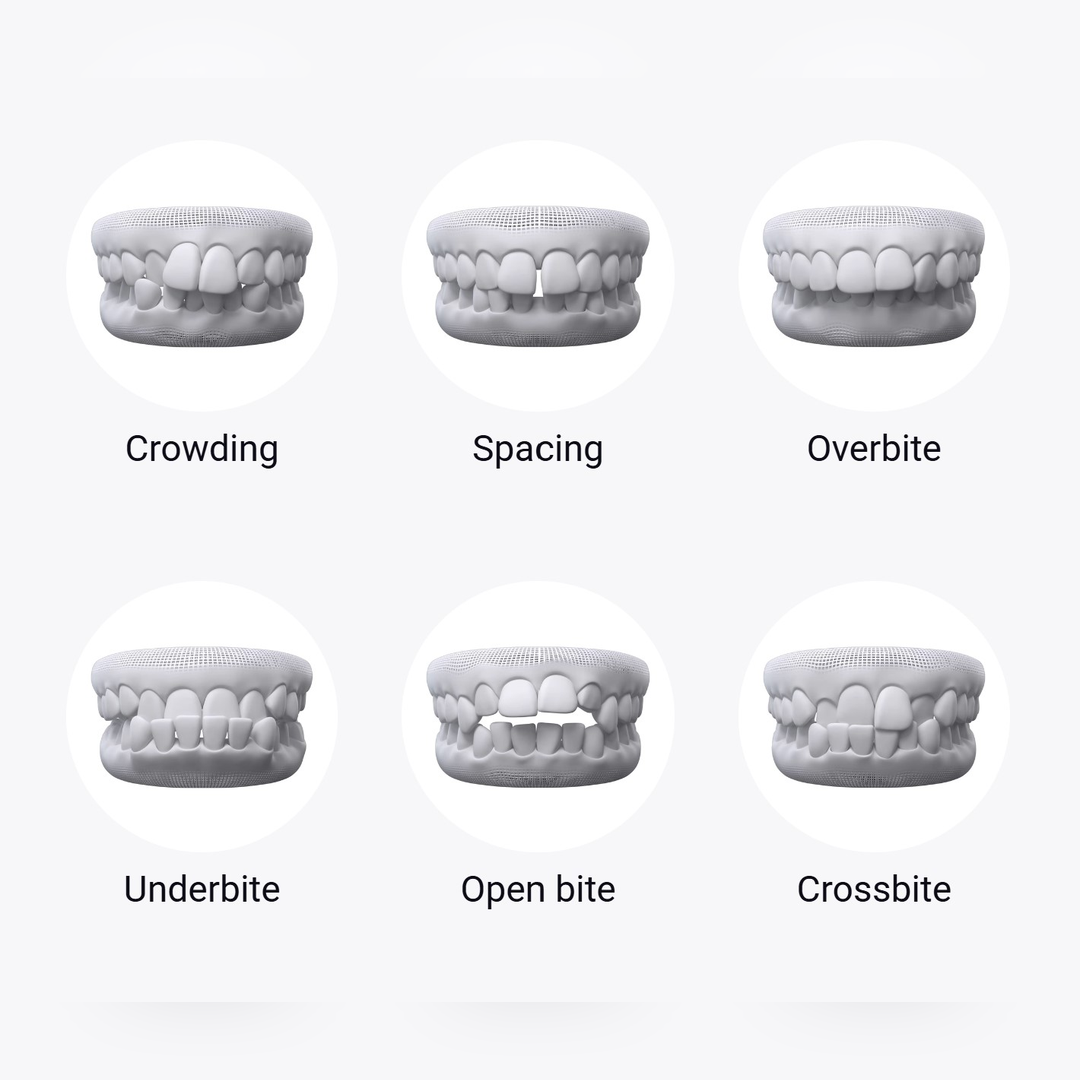

Dental braces (Teeth Clip) correct several orthodontic issues, including:

Clear aligners work well for many common concerns such as crowded teeth, gaps, overbite, underbite, and mild to moderate misalignment. They are especially popular among adults and young professionals who want a subtle treatment option. However, very complex cases may still require traditional braces or a combination of treatments.